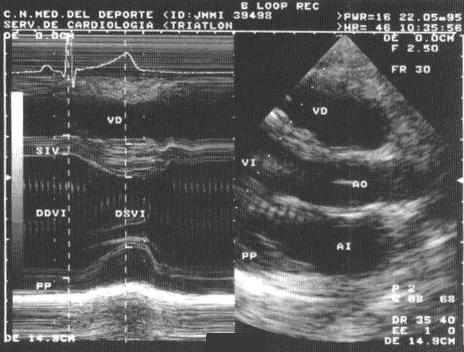

El corazón responde al estímulo de diferentes modalidades de ejercicio con adaptaciones que facilitan el rendimiento cardiaco ante el estrés […]

Los valores de referencia de las distintas adaptaciones asociadas a diferentes modalidades deportivas son esenciales para entender mejor las respuestas